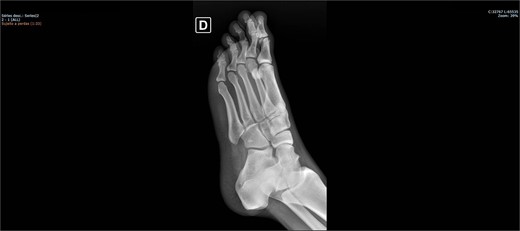

The patient was placed on the surgical table in the supine position, anesthetized with spinal anesthesia, and given prophylactic antibiotic therapy with 2 g of cefazolin. After exsanguination of the lower limb, a dorsolateral incision was made on the foot over the cuboid bone and deepened through the layers until complete visualization of the cuboid bone was achieved. There was an interposition of ligamentous structures, such as the calcaneocuboid ligament, dorsal cuneocuboid ligament, and dorsal tarsometatarsal ligaments. After removing all structures that were interposed and preventing reduction, the cuboid was reduced easily, but instability was observed. Due to the instability found, percutaneous fixation was performed with three Kirschner wires: the first extending from the fourth metatarsal to the calcaneus, traversing the cuboid; the second from the fifth metatarsal to the cuboid; and the third from the cuboid to the calcaneus, from anterior-dorsal to posterior-plantar (Figs 3 and 4). After complete fixation, the stability of the cuboid was observed, maintaining it in the correct position, confirmed with fluoroscopy during surgery.